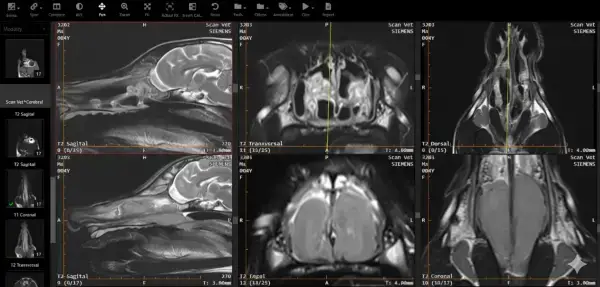

Dr. Moscu: Când chirurgia repetată nu a adus rezoluția unei polipoze nazale extrem de agresive, recidivante, care bloca complet cavitățile nazale iar analizele histopatologice nu au reușit să aducă informația diagnosticării precise atât de necesară, cu deținători devotați, capabili de orice efort material, soluția a venit dinspre tratamentul citostatic. Pentru mine și deținători, imaginile din rândul doi au în subsidiar disperarea, dezamăgirea, sentimentul neputinței de a ameliora măcar situația, de a vedea suferința dată de imposibilitatea cățelului de a respira nazal, de a se odihni corespunzător. Imaginile din primul rând, la două luni de tratament citostatic exprimă pentru toți cei implicați emoția debordantă a speranței în reușită, emoția speranței unei vieți trăite normal, fără suferință, cu bucurie, în familia cu oameni buni și iubitori. Tratamentul se desfășoară deja de un an, cu ajutorul și bunăvoința colegilor din localitatea de reședință, acum fiind pe o schemă redusă, starea generală este perfectă iar analizele fără nici o abatere de la normal. Privesc imaginea și știu că și așa poate arăta emoția. De asemenea țin să le mulțumesc tuturor colegilor care s-au implicat și cu care simt nevoia să o împărtășesc.